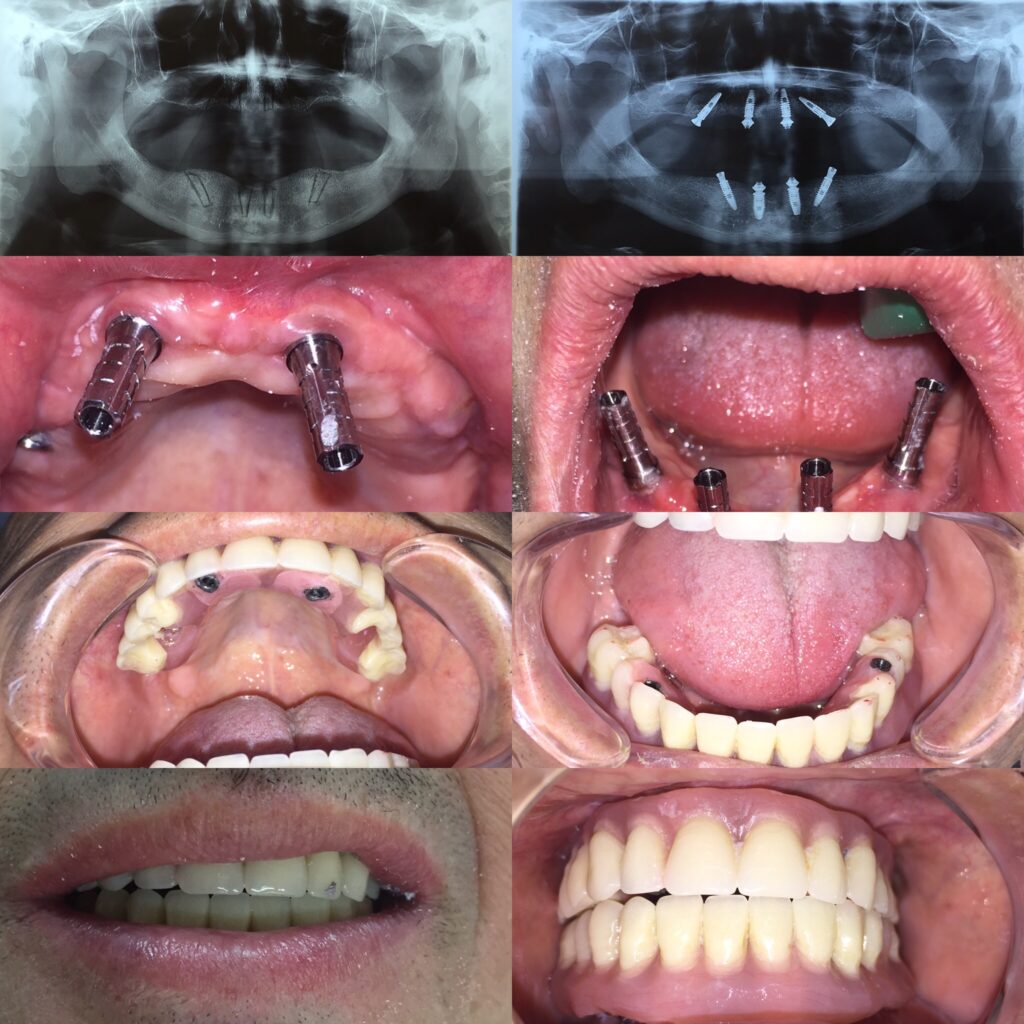

Los implantes dentales, el injerto de hueso y la rehabilitación fija son procedimientos dentales que se relacionan entre sí:

- Injerto de hueso: Se realiza para que el implante dental se una de forma sólida al hueso del paciente, un proceso llamado osteointegración. Este procedimiento se realiza mediante una cirugía en la que se coloca material de regeneración entre el hueso y la encía. El material se integra al hueso del paciente y aumenta su volumen. La recuperación puede tardar entre 3 y 12 meses.

- Implantes dentales Son pequeños tornillos de titanio que se insertan en el hueso alveolar para sustituir a las raíces de los dientes. Una vez que el implante se osteointegra, se fabrica una prótesis que se fija a un aditamento protésico atornillado al implante.

- Rehabilitación fija Es un método clínico que consiste en colocar un aparato fijo que se une a los dientes naturales o a los implantes dentales para restituir los dientes perdidos.

El injerto de hueso es necesario para colocar implantes dentales cuando el hueso dental no tiene el volumen suficiente. De esta forma, el paciente evita tener que usar prótesis removibles.